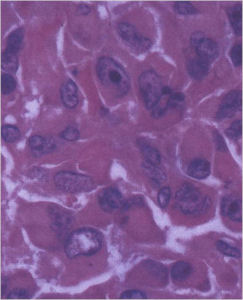

Aggressive Osteoblastoma

- Aggressive osteoblastoma is a distinct rare type of osteoblastoma that has a much more aggressive local behavior than a conventional osteoblastoma. They have a higher chance for local recurrence after removal.

- There has been controversy about the true existence of this type of tumor and whether these tumors are actually low grade osteosarcomas.

- They have a similar appearance microscopically as a conventional osteoblastoma except the osteoblasts are twice as large and have an epithelioid quality with abundant eosinophilic cytoplasm (Epithelioid Osteoblasts).

- Aggressive osteoblastoma is a borderline lesion lesion between osteoblastoma and osteosarcoma. It is not a precursor to osteosarcoma. It does not metastasize.